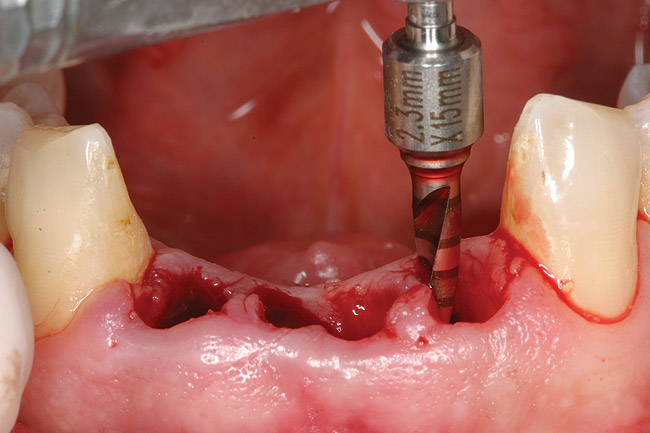

Preoperatively, 1 g of amoxicillin was administered. Using local anesthesia (lidocaine 1:100,000 epinephrine), extractions of teeth No. 23 to No. 26 were performed without raising a flap and with gentle luxation to preserve the remaining facial osseous plate. The sockets were curetted prior to implant placement. A vacuum-formed surgical guide, fabricated based on a diagnostic wax-up of the desired tooth positions for the subsequent fixed prosthesis, was used during implant placement. Osteotomies were performed at sites No. 23 and No. 26 and positioned toward the lingual aspects of the sockets (Figure 3A and Figure 3B). Two tapered implants (OsseoTite™ 313, BIOMET 3i™, Palm Beach Gardens, FL) measuring 3.25 mm x 13 mm were placed. Conical prosthetic abutments (3-mm height) were used to facilitate joining the two implants in a screw-retained fixed partial denture (Figure 4). A laboratory-processed acrylic-resin provisional restoration was altered to allow connection to the temporary cylinders. The provisional was placed into the vacuum-formed surgical guide that was now used to maintain the provisional in the correct 3-dimensional position (Figure 5) while being attached to the temporary cylinders with acrylic resin intraorally. Once a sufficient amount of acrylic resin was placed to secure the cylinders to the provisional, it was removed from the mouth and its contours were completed at the laboratory bench (Figure 6A). The two central incisor sockets were grafted with small-particle allograft material (Puros® Allograft, Zimmer Dental, Carlsbad, CA) to maintain gingival architecture beneath two ovate pontics (Figure 6B). The provisional restoration was inserted and the screws tightened to 20 Nt-cm of torque.

Figure 3a 3  Osteotomies prepared lingually.

Figure 3a

Figure 3  Placement of implants without flap elevation.

Figure 3